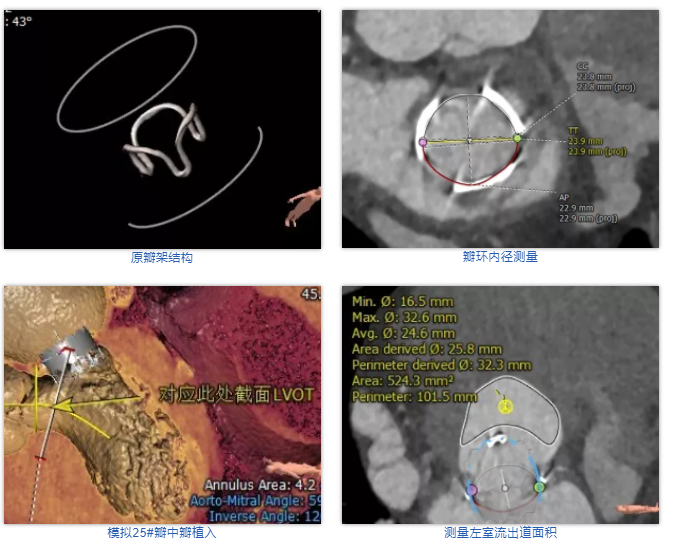

术前经详尽评估患者病情,通过CT重建测量瓣环直径、左室流出道面积。结合之前外科换瓣手术入路,最终决定采用经心尖途径行二尖瓣“瓣中瓣”手术,患者既往植入27#爱德华猪瓣,选用25# Renato®球扩式瓣中瓣。手术过程顺利,瓣中瓣植入位置理想,功能表现出色,左室造影及经食道超声观察无明显瓣中及瓣周反流。二尖瓣峰值流速由术前2.1m/s降至1.0m/s,平均跨瓣压差由7.2mmHg降至1.8mmHg。